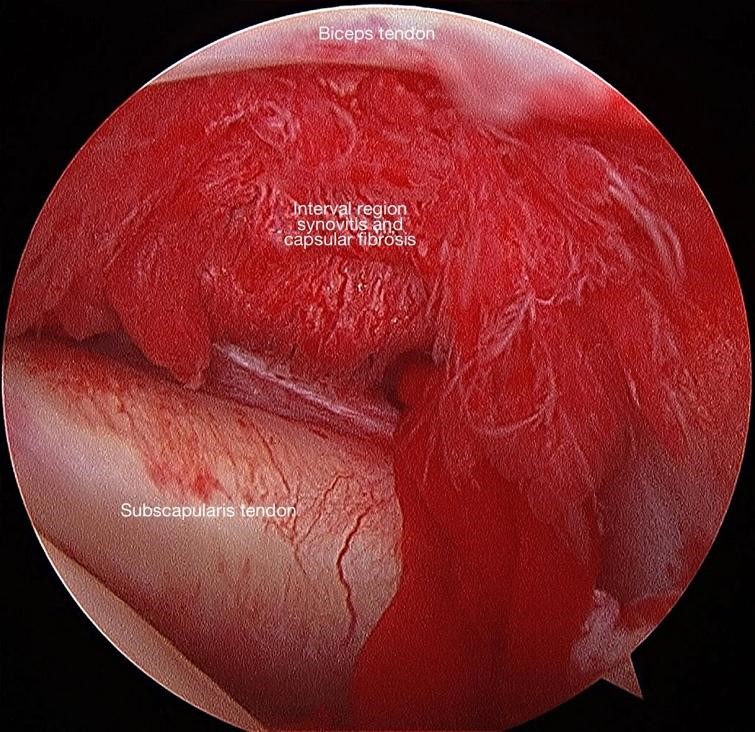

Artroszkópos hegfelszabadítás befagyott váll szindróma esetén

Nagyfokú mozgásbeszűkülés vagy a műtét nélküli kezelés sikertelesége esetén kifejezetten ajánlott a befagyott váll szindróma során kialakult hegek sebészi úton történő oldása, melyet artroszkópos technikával végzünk. Ez az eljárás kombinált érzéstelenítést (altatás és regionális érzéstelenítés) igényel és körülbelül 30 percig tart. A betegek még aznap hazamehetnek. A műtét során két-három kis bemetszést ejtünk a vállon, bevezetünk egy kamerát az ízületbe, illetve a hegek feloldására alkalmas speciális eszközöket, melyekkel elvégezzük az összenövések feloldását. Az eljárás hosszú távú eredménye nagyon jó és a szövődmények kockázata minimális. Bár a mozgás azonnali javulása bekövetkezik, a teljes felépülés még mindig 4-6 hónapot vesz igénybe. A beavatkozás után azonnal el kell kezdeni a fizikoterápiát és arra kérem a pácienseimet, hogy a napi nyújtás mellett hetente háromszor vegyenek részt szakember által irányított gyógytornán három héten keresztül.